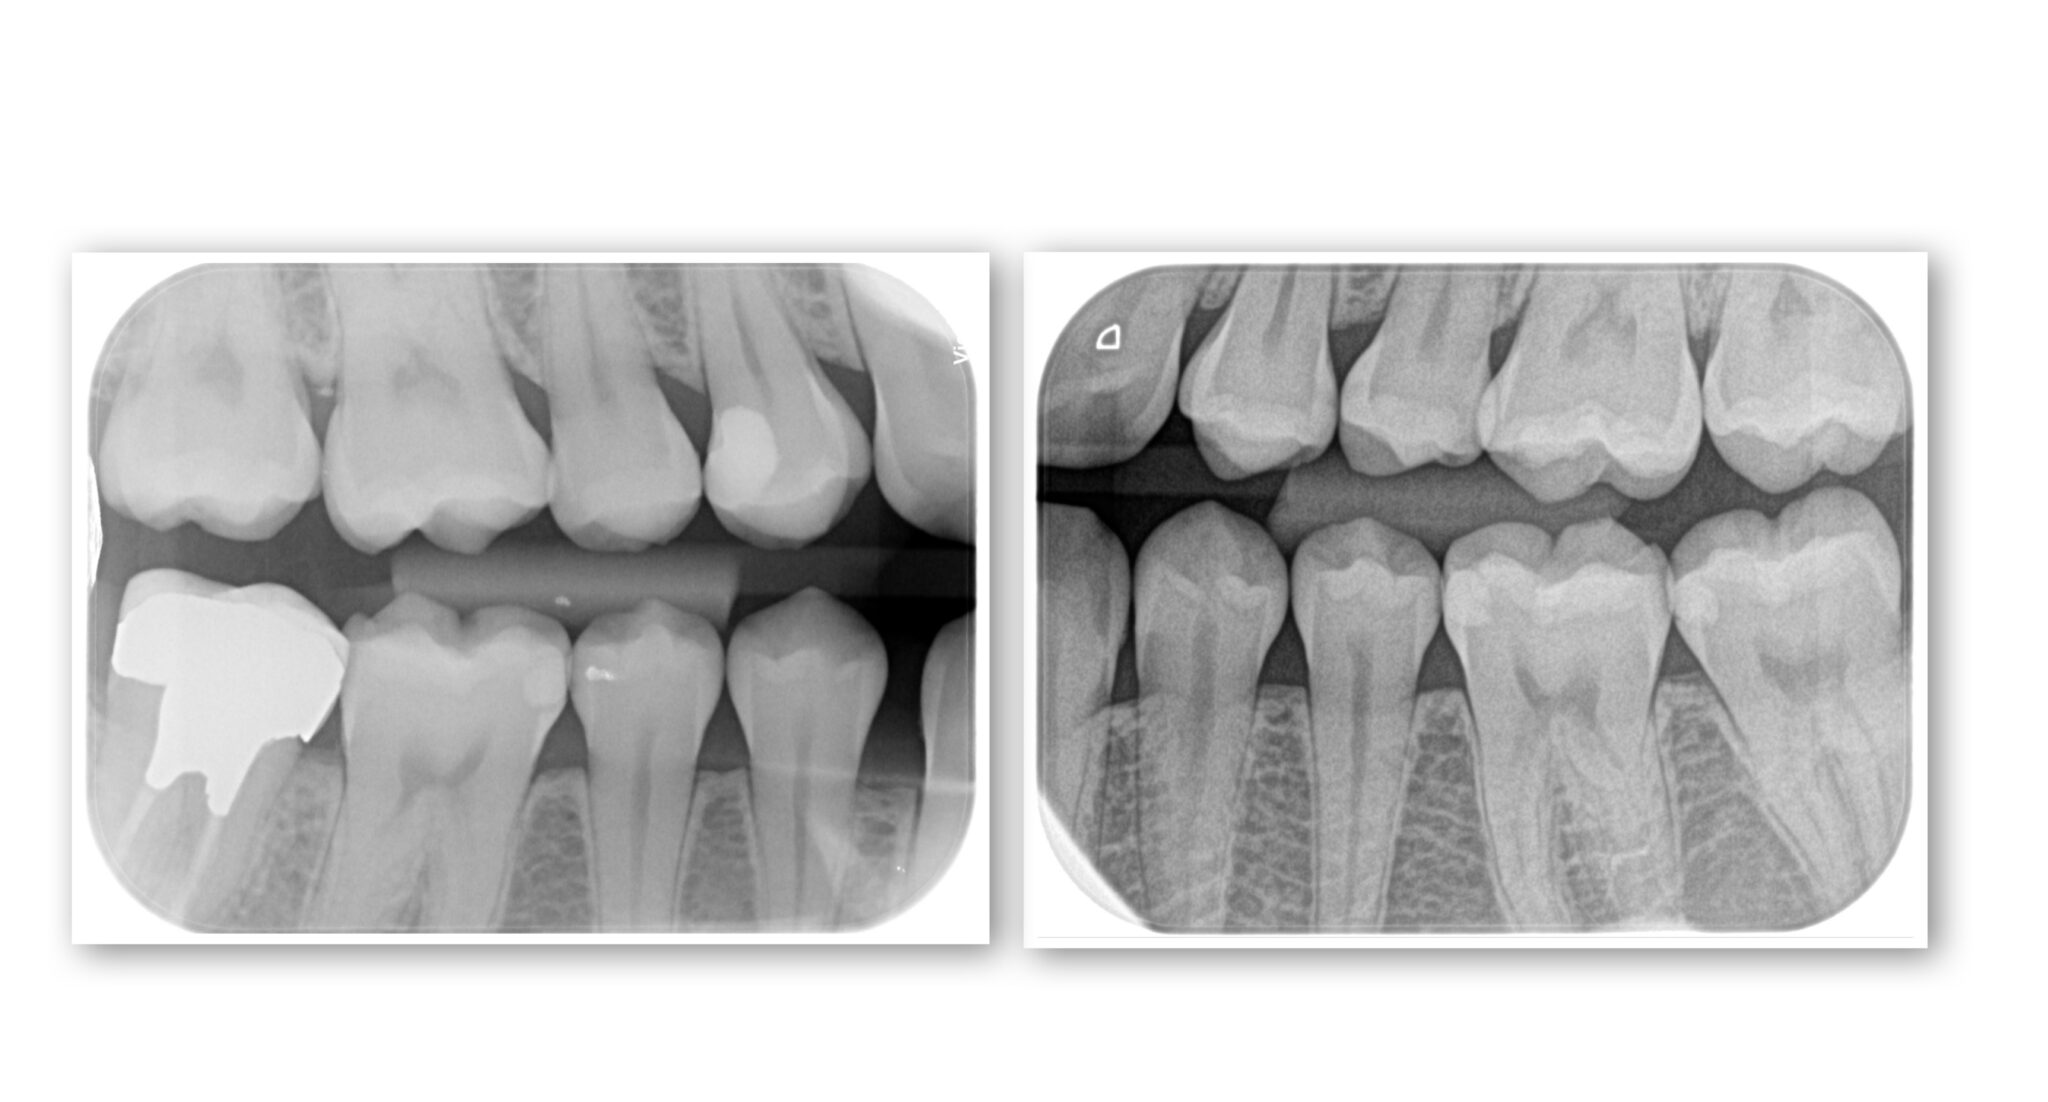

咬翼法X線撮影は、奥歯の虫歯や歯石の検出に優れます。

咬翼法X線写真